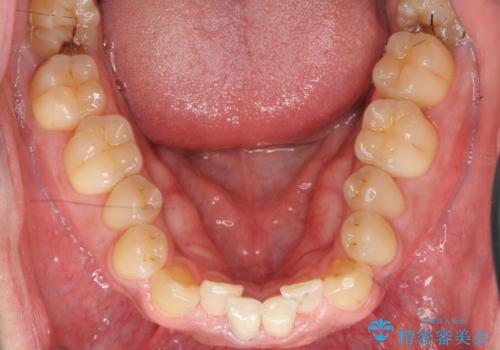

神経が死んでいる歯の根管治療を行った後、セラミッククラウンによる補綴治療を行いました。

比較的短期間(2ヶ月、来院回数:5回)で治療が終わったこと、また自然な仕上がりと使用感にご満足頂けました。

ジルコニアクラウン スタンダード